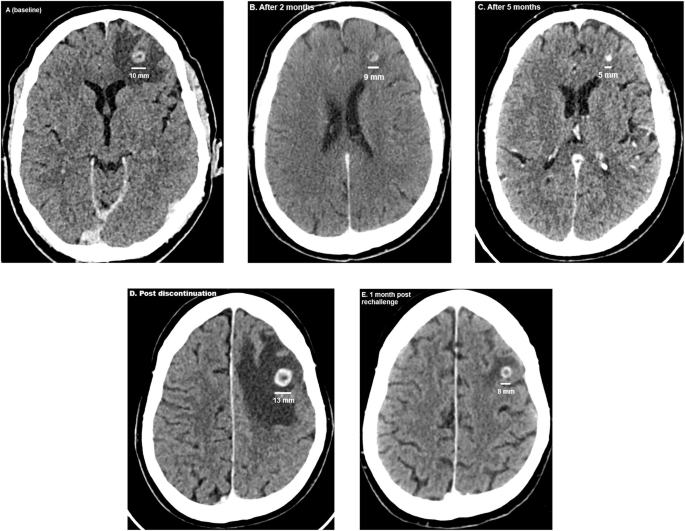

At baseline, the two BrM had a diameter of 10 and 5 millimeters (mm) surrounded by oedema (Fig. 1A). After two months of cabozantinib/nivolumab, on CT-scanner the largest BrM measured 9 mm and the smallest BrM was barely detectable (Fig. 1B). After 5 months, the largest BrM had shrunk to 5 mm and the smaller BrM was no longer visible, with significantly diminished oedema (Fig. 1C). The peritoneal implants showed a decrease in volume, while extracranial disease in other locations remained unchanged. After 8 months, the diameter of the largest BrM was 4 mm. Progression at the level of fifth dorsal vertebra led to embolization and tumor debulking with hemilaminectomy and pediculectomy. Cabozantinib was interrupted peri-operatively. Due to postoperative complications adjuvant RT on the fifth dorsal vertebra was postponed and cabozantinib discontinued longer. Two months later, the patient presented with speech disorders, dysarthria and word-finding problems. On CT scan, the largest BrM had increased to 13 mm and multiple new BrM had emerged (Fig. 1D). Cabozantinib was restarted at 40 mg/day. After 1 month of cabozantinib, the largest lesion had decreased to 8 mm (Fig. 1E). After 4 months of cabozantinib, this BrM measured 5 mm and the other BrMs as well as the oedema had resolved. At the thoracoabdominal level, the disease remained stable.

A–E Evolution of the largest brain metastasis. A At start of cabozantinib. B and C Response on cabozantinib. D: Increase of the diameter after two months of cabozantinib discontinuation. E Response after rechallenge of cabozantinib.